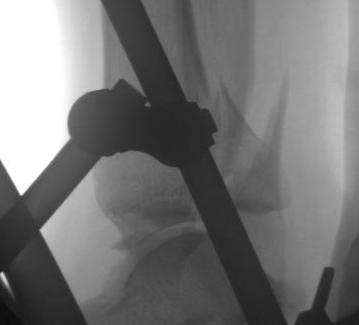

Indirect reduction and AP screws

1. Indirect reduction and AP screws - small fragment that can be reduced

- malreduction defined as > 2 mm articular step off

- indirection reduction: 24%

- open reduction: 8%